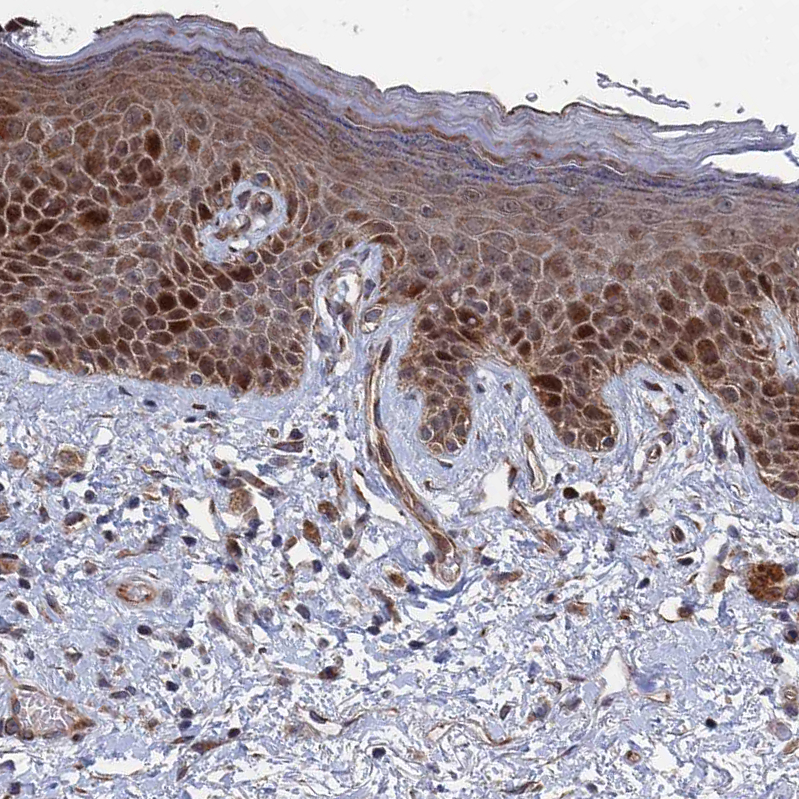

Immunohistochemical staining of human skin shows moderate to strong cytoplasmic and nuclear positivity in squamous epithelial cells.